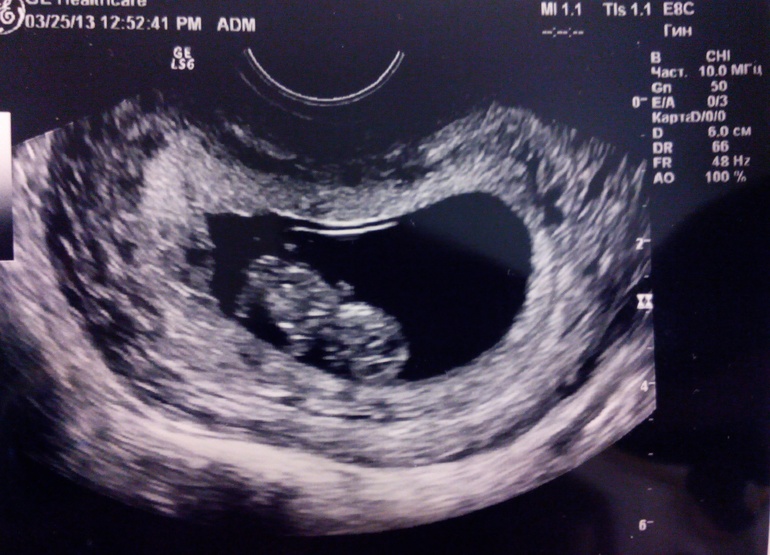

Олечка 11 лет Первое узи нашей второй крохи)) Сегодня 9 с половиной недель по узи. Все отлично, как и положено. Посмотрите еще 20 записей на эту тему Отменить Ответить Марина Поздравляю с хорошим узи!!! Растите здоровенькими!!! 27.03.2015 Ответить Ведана мама десятерых Поздравляю) 27.03.2015 Ответить Очень вкусный тортик?????? Кирюшка ходит!!!! Чаты Беременных Выберите чат: Январята-2026 Февралята-2026 Мартята-2026 Апрелята-2026 Майчата-2026 Июнята-2026 Июлята-2026 Августята-2026